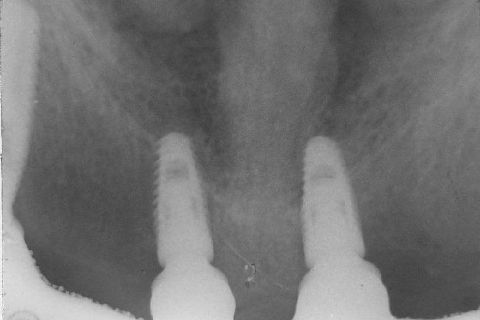

Atualização do caso clínico que já postei, "REABILITAÇÃO EM MAXILA ATRÓFICA COM IMPLANTES", um caso que inclui expansão do rebordo estreito com cinzel e martelo, expansores rosqueáveis, enxerto e instalação dos implantes distais inclinados tangenciando seio maxilar. Inclui esvaziamento do forame nasopalatino e preenchimento com biomaterial para instalação de dois implantes próximos dele. Cirurgia realizada em única sessão, com instalação dos 6 implantes. Para os colegas que não conheceram e/ou esqueceram da apresentação, este é o resumo do caso na fase cirúrgica.http://www.youtube.com/watch?v=BtvexFexRPA&hd=1

FASE PROTÉTICA DA REABILITAÇÃO EM MAXILA ATRÓFICA...incluindo a reabertura, instalação dos minipilares e PTR provisória reembasada sobre os cilindros de proteção.